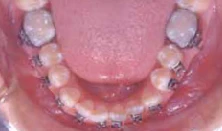

Hình 11a Một ví dụ lâm sàng của gắn mắc cài xoay. Điều chỉnh hoàn toàn sự xoay có thể đạt được trong giai đoạn sớm của điều trị mà không cần thêm phương pháp đặt biệt nào khác. Xem thêm Hình 11b.

Hình 11b